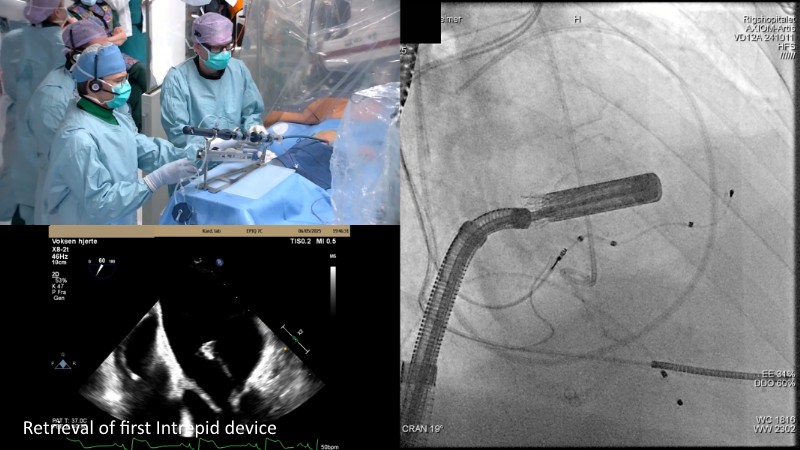

This EuroPCR 2025 session highlights the evolving role of transcatheter mitral valve replacement, focusing on the clinical potential of mitral regurgitation elimination. Get an overview of the current status of the Intrepid TMVR programme, learn about the transition to the 29Fr transfemoral system, and explore how patient screening—especially in the presence of mitral annular calcification—impacts procedural planning. Real-world case reviews from the APOLLO-EU trial offer practical insights into how this next-generation system is being applied in Europe today.